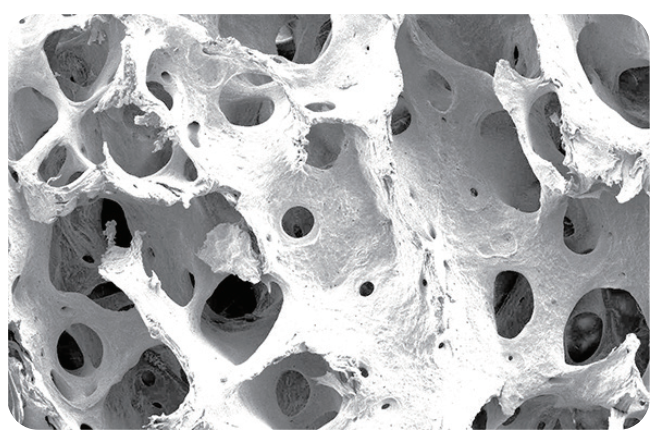

为牛松质骨经过脱细胞,脱脂等处理(易岭独特的专利技术[专利号:ZL202110089289.9])后形成的骨基质,属于脱细胞基质类再生材料,呈白色略带黄色块状或颗粒状,保留了天然的三维多孔结构,主要成分是I型胶原蛋白。

双峰多孔结构,孔隙率高达80%,优化了材料的毛细作用,同时保障了血液中成骨细胞和生长因子的募集,确保有效骨融合。

诚谷快@口腔用骨填充材料和人体骨组织结构高度相似,为血管再生和新骨沉积(成骨)提供充足空间。多种直径微孔隧道结构技术保证了诚谷快口腔用骨填充材料良好的毛细作用,从而能迅速摄取液体(血液);相互连通大孔允许各种细胞和生长因子进入,结合并储存蛋白质和生长因子,为骨融合提供了必要的生物环境和生长因子支持引导自体骨的自然改建。